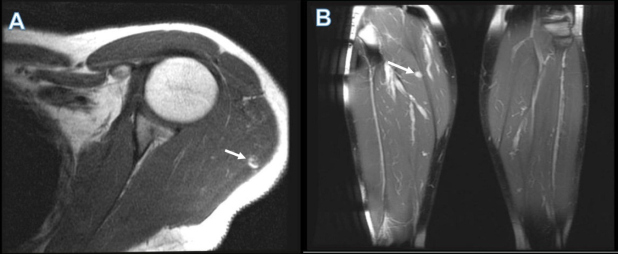

Es llevado a tiroidectomía total con vaciamiento ganglionar central y bilateral de cuello. El reporte anatomopatológico informa carcinoma papilar de tiroides de patrón clásico, multifocal, pT2(m), pN1b, cM1, Estadio II, con alto riesgo de recurrencia. Se indicó terapia con 7400 MBq (200 mCi) de I-131, con estudios bioquímicos que evidenciaron TSH 14,8 uUI/ml, tiroglobulina 500 ng/ml y anticuerpos antitiroglobulina negativos. Se realizó rastreo corporal total de control (Fig. 1), encontrándose dos restos tiroideos además de compromiso metastásico pulmonar y áreas yodocaptantes en húmero proximal y fémur izquierdo, coxofemoral ipsilateral y tibia derecha. Con el objetivo de realizar correlación anátomo-funcional se decidió solicitar resonancia magnética (RM) de hombro izquierdo, pelvis y miembros inferiores (Fig. 2). Se evidencia lesión intramuscular en la porción posterior del músculo deltoides izquierdo y lesión con captación de medio de contraste en músculo sóleo derecho, las cuales son concordantes con los hallazgos descritos en el rastreo corporal total y sugestivas de compromiso metastásico.

El paciente continuó en seguimiento médico, realizándose control con perfil bioquímico que evidenció TSH suprimida (0,25 uUI/ml), tiroglobulina en descenso (172 ng/ml) y anticuerpos antitiroglobulina negativos, además de tomografía de tórax que según criterios RECIST 1.1 presentaba respuesta parcial de las lesiones pulmonares. Se indicó biopsia de las lesiones sospechosas en región deltoidea izquierda y sólea derecha, las cuales no fueron susceptibles a este procedimiento por su disminución de tamaño y dificultad técnica para obtener una muestra. Se decidió administrar nueva terapia con 3700 MBq (100 mCi) de I-131 realizándose rastreo corporal de control con tomografía por emisión de fotón único de (SPECT) e imagen de fusión con RM previa de hombro izquierdo (Fig. 3).

Se observó persistencia de captación en campos pulmonares, además de disminución de las lesiones yodocaptantes en región deltoidea izquierda y tibial proximal, con desaparición de la captación en fémur izquierdo (Figs. 4 y 5). Con este resultado, se realizó RM de control de hombro izquierdo y miembros inferiores, visualizándose disminución en el tamaño de las lesiones.